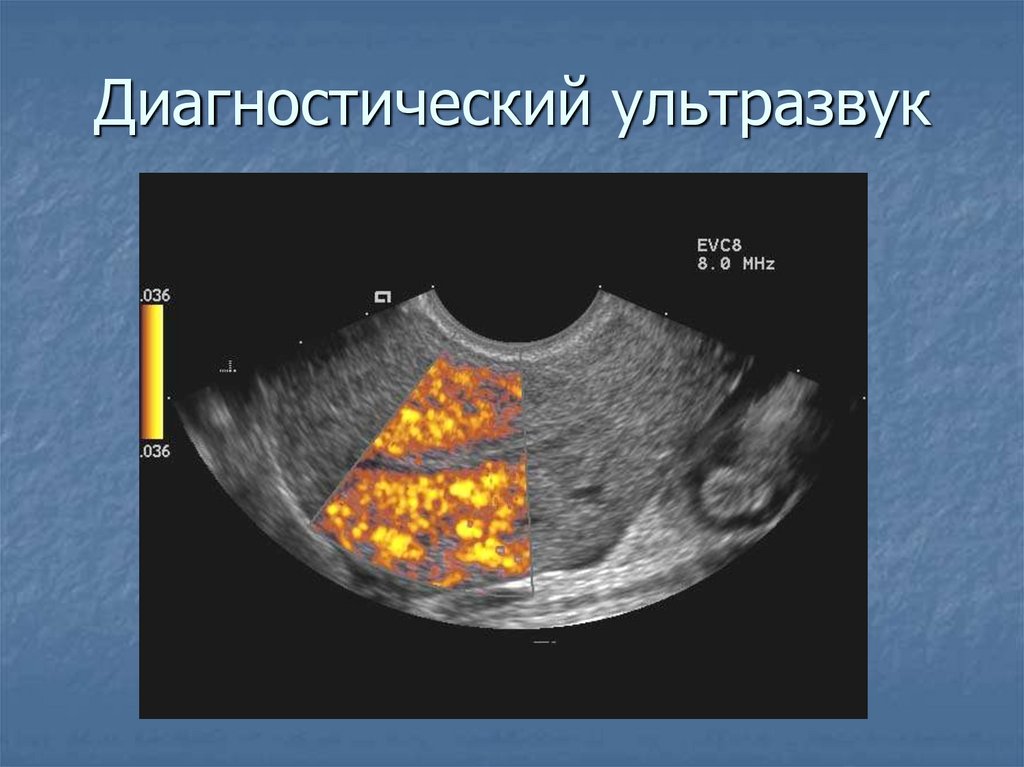

Приборы для доплерографии

ВОЗМОЖНОСТИ ЦДК